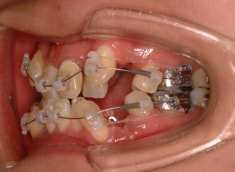

治療法:表の矯正(T21ブラケット)

ご出産のため治療中断期間あり

骨格的な下顎前突の傾向は強くはありませんが、歯牙の状態によって反対咬合が認められます。LowTongue(低位舌)もあります。

修復歯、補綴歯もあります。下顎8番が水平埋伏しています。